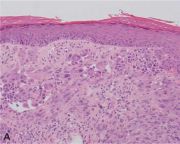

| 06:08, 31 באוקטובר 2023 | Myocarditis3.jpg (קובץ) |  |

130 קילו־בייטים | Motyk | 1 | |

| 14:51, 30 באוקטובר 2023 | Myocarditis2.png (קובץ) |  |

64 קילו־בייטים | Motyk | 1 | |

| 13:08, 30 באוקטובר 2023 | Myocarditis1.png (קובץ) |  |

235 קילו־בייטים | Motyk | 1 | |

| 12:06, 30 באוקטובר 2023 | Myocarditis4.jpg (קובץ) |  |

142 קילו־בייטים | Motyk | 1 | |